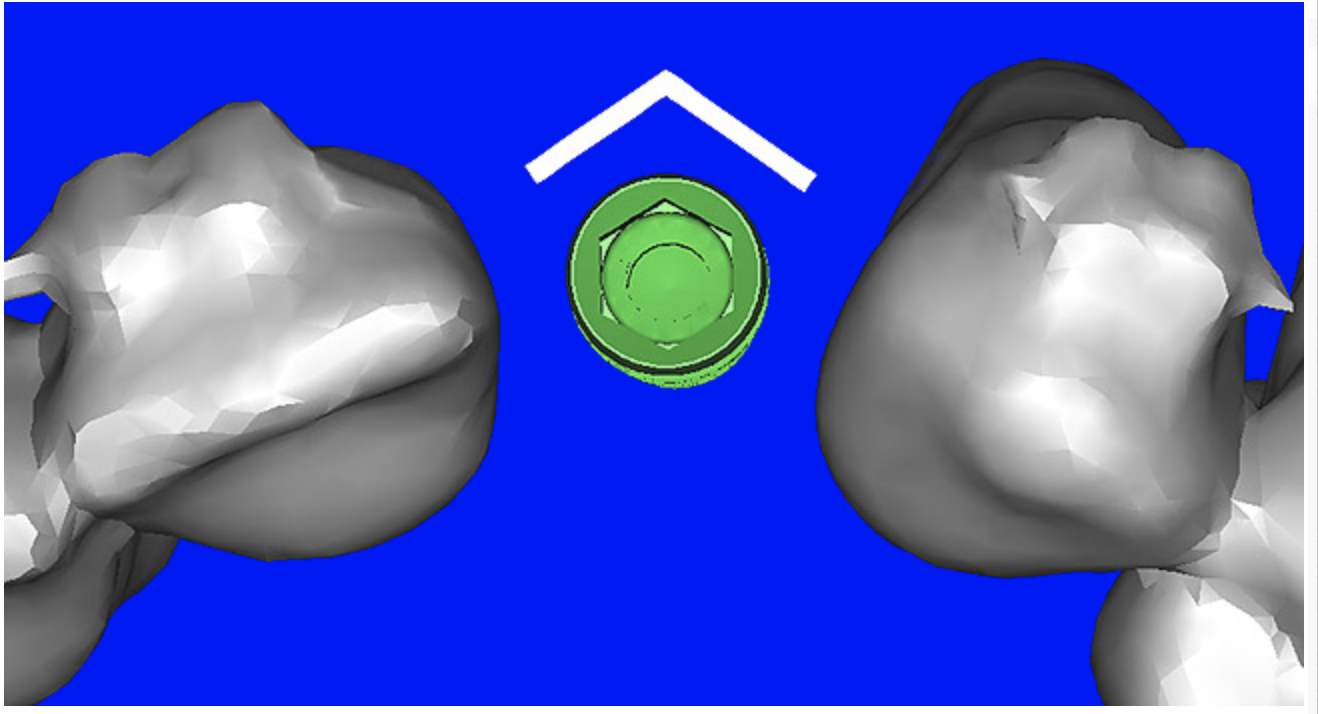

Using different masking (segmentation) and threshold Hounsfield unit values, several new 3D bone volumes can be created which offer invaluable information. To help determine the final position of each implant a new bone model was created with a Hounsfield unit value of 1480, which eliminated all but the densest objects included in the scan data. (Results may vary depending on the CBCT machine used.) The inner and outer layers of bone were removed, leaving the underlying enamel and root structure of the teeth (Figure 8A). After the bone had been stripped away, the root inclinations were examined closely. The most striking findings confirmed the rotated position of the right central, while revealing the slight mesial dilaceration of the root apex, which converged on the space needed for the path of the potential implant (Figure 8B). The schematic shapes of the proposed implants were visualized for the right and left lateral spaces in different rotations of the 3D maxillary arch. It was at this point that a determination was made as to the appropriate implant shape and type that would fit the available space while avoiding encroachment on adjacent tooth roots. A tapered design implant (Tapered Screw-Vent®, Zimmer Dental, www.zimmerdental.com) was chosen from the large virtual library. With the SIMPlant software, the virtual library contains data from dozens of implant manufacturers and realistic computer-aided design representations as seen in Figure 9A through the translucent bone. The position of the left implant can be visualized with adequate mesial-distal distance between adjacent tooth roots (Figure 9B) and a more delicate placement (Figure 9C).

Figure 9a  Virtual implants were placed to determine the appropriate shape and type for the available space; in this case a tapered design allowed for adequate mesial-distal distance between adjacent roots.

Figure 9b  Virtual implants were placed to determine the appropriate shape and type for the available space; in this case a tapered design allowed for adequate mesial-distal distance between adjacent roots.

Figure 9c  Virtual implants were placed to determine the appropriate shape and type for the available space; in this case a tapered design allowed for adequate mesial-distal distance between adjacent roots.